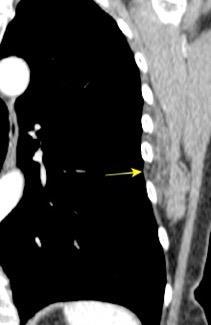

50% de los tumores de partes blandas.

Predilección varones en lipomas profundos

30% “hereditarios”

Isointenso con grasa subcutánea

Burt AM et al. Imaging review of lipomatous musculoskeletal lesions. SICOT J2017/ Murphey MD et al. From the archives of the AFIP: benign musculoskeletal lipomatous lesions. Radiographics. 2004